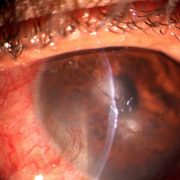

Slitlamp Imaging

Using a beamsplitter, SLR mount and a DSLR camera capture in 18MP (or higher) to get a superior quality image perfect for patient data collection, review and HD live display. Record video clips in full HD.